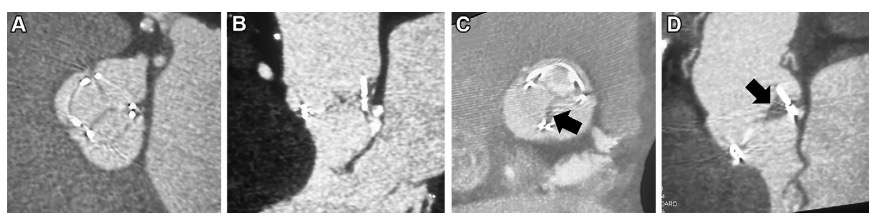

瓣膜植入术后的心脏 CT 还发现了瓣叶上形成的生物瓣膜血栓,即低增强瓣叶血栓(hypoattenuating valve leaflet thrombus/ hypoattenuating leaflet thickening, HALT)。

2015 年首次描述了HALT,目前对于HALT的认识仍在不断发展

如下图所示正常的TAVR叶和HALT:

(A,B)76岁男性TAVR多平面重建显示舒张期正常TAVR叶

(C,D)84岁男性外科主动脉瓣置换术的多平面重建显示的非冠状瓣叶的异常增厚(abnormal thickening of the noncoronary leaflet)(箭头),据此可以推断出现了HALT。

这种HALT并发症可能出现在经导管和外科生物人工瓣膜上,使用抗凝治疗后即可缓解。

当HALT限制瓣叶运动时,称为影响运动的低增生( hypoattenuation affecting motion, HAM),HAM的发生可能会导致瓣膜流出道阻塞。

4D心脏 CT 使用整个心动周期的扫描数据来创建瓣叶运动的电影环路,能够有助于识别 HAM 并确定其特征,同时将其与造成手术后瓣膜坡度的其他原因(如瓣膜囊肿)区分开来。